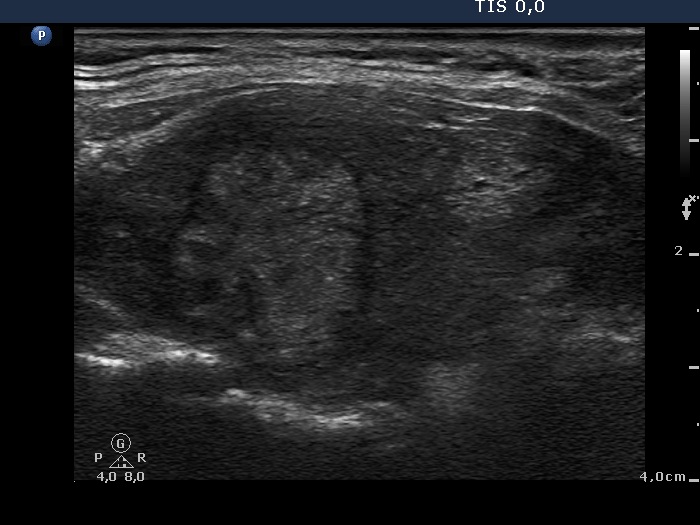

Graves' disease - case 1147 (ultrasonographic picture 6)

Left lobe, longitudinal scan. The two nodules in hypoechogenic background.